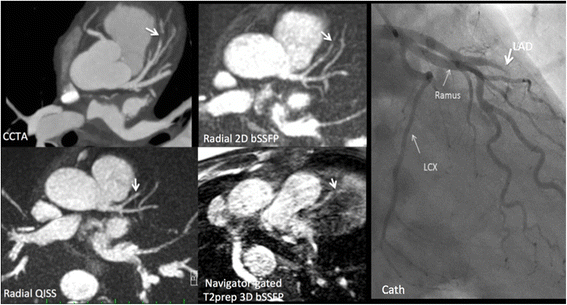

Methods: The left coronary circulation was imaged in six healthy subjects and two patients with coronary artery disease. Breath-hold QISS was compared with T2-prepared 2D balanced steady-state free-precession (bSSFP) and free-breathing, navigator-gated 3D bSSFP.

Results: Approximately 10 2.1-mm thick slices were acquired in a single ~20-s breath-hold using two-shot QISS. QISS contrast-to-noise ratio (CNR) was 1.5-fold higher at 3 Tesla than at 1.5 Tesla. Cartesian QISS provided the best coronary-to-myocardium CNR, whereas radial QISS provided the sharpest coronary images. QISS image quality exceeded that of free-breathing 3D coronary MRA with few artifacts at either field strength. Compared with T2-prepared 2D bSSFP, multi-slice capability was not restricted by the specific absorption rate at 3 Tesla and pericardial fluid signal was better suppressed. In addition to depicting the coronary arteries, QISS could image intra-cardiac structures, pericardium, and the aortic root in arbitrary slice orientations.

Conclusions: Breath-hold QISS is a simple, versatile, and time-efficient method for coronary MRA that provides excellent image quality at both 1.5 and 3 Tesla. Image quality exceeded that of free-breathing, navigator-gated 3D MRA in a much shorter scan time. QISS also allowed rapid multi-slice bright-blood, diastolic phase imaging of the heart, which may have complementary value to multi-phase cine imaging. We conclude that, with further clinical validation, QISS might provide an efficient alternative to commonly used free-breathing coronary MRA techniques.